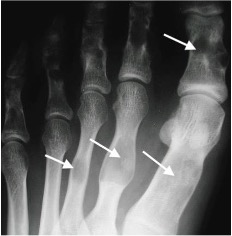

Multiple enchondromas (arrows) in Ollier’s disease

Enchondroma

- Benign cartilaginous tumour

- Typically found in the diaphyses of the metatarsals and phalanges

- Well defined, radiolucent and mildly expansile with cortical thinning

- May have internal calcification

- Multiple enchondromas (as seen in Ollier’s disease) may have malignant potential